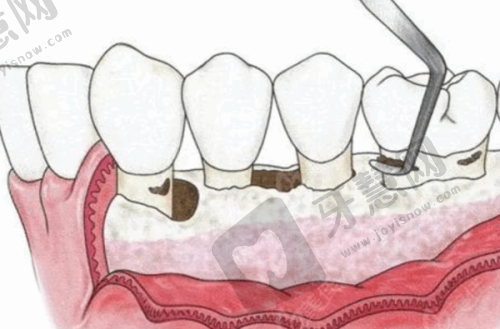

北京韩国登腾Dentium种植牙医院特色众多,比如北京钛植口腔,专注种植专科,有经验多的院长坐镇,能开展高难度手术;北京牙元素口腔,采用全数字化种植导板定位技术,为骨量不足患者提供保护;北京极简海德堡口腔,运用3D导板导航技术,实现当天种牙当天戴冠;北京整齐娃娃口腔,价格实惠,种植成效美观;北京科尔口腔,骨增量技术解决牙槽骨萎缩问题;北京劲松口腔医院,连锁规模大,技术全方面,糖尿病、高血压患者也能种牙;北京启康口腔,术前术后服务周到,拔牙即种省时省心;北京瑞泰口腔,数字化技术缩短种植疗程;北京美冠塔口腔,专注中老年口腔服务;北京瑞齿口腔门诊部,设备齐全,严格消毒;北京中 医 药大学东直门医院口腔科,国有医院,医生实力强;北京大学口腔医院第三门诊部,非营利性且医疗保险定点,医生学历高;北京中诺口腔医院和北京海淀中诺口腔医院,连锁优势明显,价格亲民;北京伶俐口腔门诊部,数字化诊疗服务社区居民。

北京牙元素口腔的韩国登腾Dentium种植牙亮点:北京牙元素口腔采用全数字化种植导板定位技术,可精细避开神经血管,适合骨量不足人群。韩国登腾Dentium种植牙是其服务项目之一,还有瑞士进口种植牙1680元起,All - on - 4半口套餐5万起,含术后免费复查服务。它就像贴心的“口腔卫士”,提高了种植安心性和精细度,术后复查服务让人放心,但有名度相对大型连锁医院稍低。

北京极简海德堡口腔的韩国登腾Dentium种植牙特色:北京极简海德堡口腔秉承“极简、精细、舒适”理念,在韩国登腾Dentium种植牙上运用3D导板导航技术,减少误差。与德国院校合作引进新技术,实现当天种牙当天戴冠。限时优惠活动中,德国数字化种植牙5000元起,高端瑞士瑞锆种植体7800元,预约送CT检查。这家医院如同“科技先锋”,提高了种植效率和舒适度,但高端种植体价格较高。